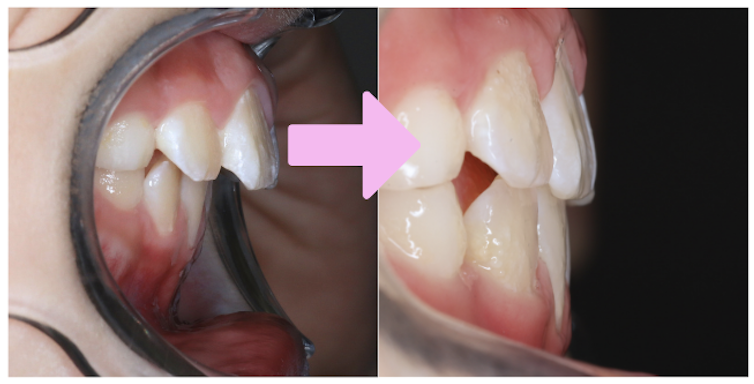

前回症例紹介させていただいた男の子同様、

歯の重なりは少ないですが、噛み合わせの深さ(オーバーバイト)が5mmありました。

理想的な数値はだいたい2〜3mm程度が目安となります。

検査時に、過蓋咬合であることが数値上でも確認できました。

噛み合わせの深さ(オーバーバイト)は、スタートから4ヶ月で5mmから2mmの数値改善が見られました!

以降も取り組みを頑張ることで理想的な数値を維持できており、開始から1年2ヶ月経った現在の写真を見ても、噛み合わせが浅くなってきていることが分かりますね。